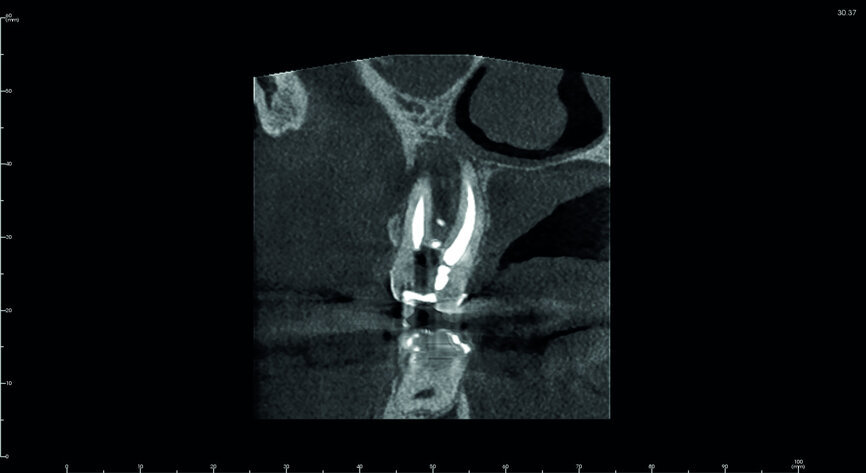

Fig. 5: Pre-op CBCT scan, sections.

A 47-year-old male patient in a good medical condition and a non-smoker was referred to our dental practice for endodontic retreatment of the right maxillary second molar. The dental history revealed that the tooth had been endodontically treated three months before because of acute pulpitis. After the treatment, the patient complained of pain on chewing. Antibiotics and a non-steroidal anti-inflammatory drug were prescribed, but the pain remained. After a month, a sinus tract appeared. The tooth was retreated in another practice without success. The clinical inspection revealed the presence of a sinus tract near the apical region of tooth #17. The tooth had been prepared for a full crown, but was without even a temporary crown, and the access cavity had been closed with temporary filling material. Cracks were evident on the buccal and mesial surfaces. Periodontal probing showed a deep pocket (> 12 mm) on the distal aspect of the root trunk (Figs. 1 & 2). The periapical radiograph showed a radiolucency between the roots of the second and third molars. The radiographic appearance of the endodontic treatment was good, without clear evidence of periapical radiolucencies (Fig. 3). A perforation of the pulp chamber floor was suspected. A CBCT scan was performed (Figs. 4–7), and it confirmed the suspicion of perforation, along with the presence of a large periradicular radiolucency and an unfavourable root shape.

The treatment plan was discussed between the authors of this paper. According to the prognostic classification of Gorni and Gagliani, it was a tooth with a modified anatomy due to previous endodontic treatment and with a 47 per cent possibility of successful retreatment. [12] The prognosis is dependent on the presence of bacterial infection of the perforation site, and successful treatment depends mainly on immediate sealing and prevention of infection; perforation of the furcal region of molars is especially troublesome because this causes considerable mechanical damage. [13] In this case, bacterial infection had been present for almost one year. The prognostic factors did not recommend any retreatment attempt, and the surgical option was ruled out because of anatomical considerations. However, the root morphology, position and size of the crown, good bone volume and quality, and possibility of atraumatic extraction and repositioning of the donor tooth recommended avulsion and transplantation of the adjacent third molar. After a discussion with the patient, a detailed informed consent form was signed and the procedure was scheduled.